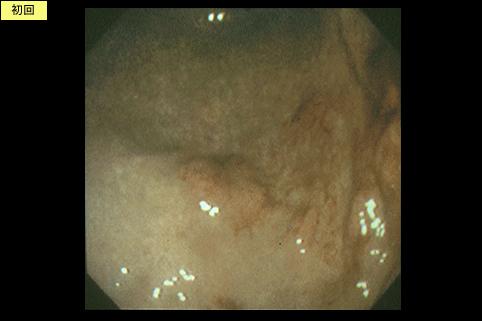

疾患(病理主体)の分類悪性リンパ系腫瘍/悪性リンパ腫

部位(臓器別)胃(部位)/体部

検査方法内視鏡

病変の最大径(ミリ)40以上

腫瘍の深達度sm